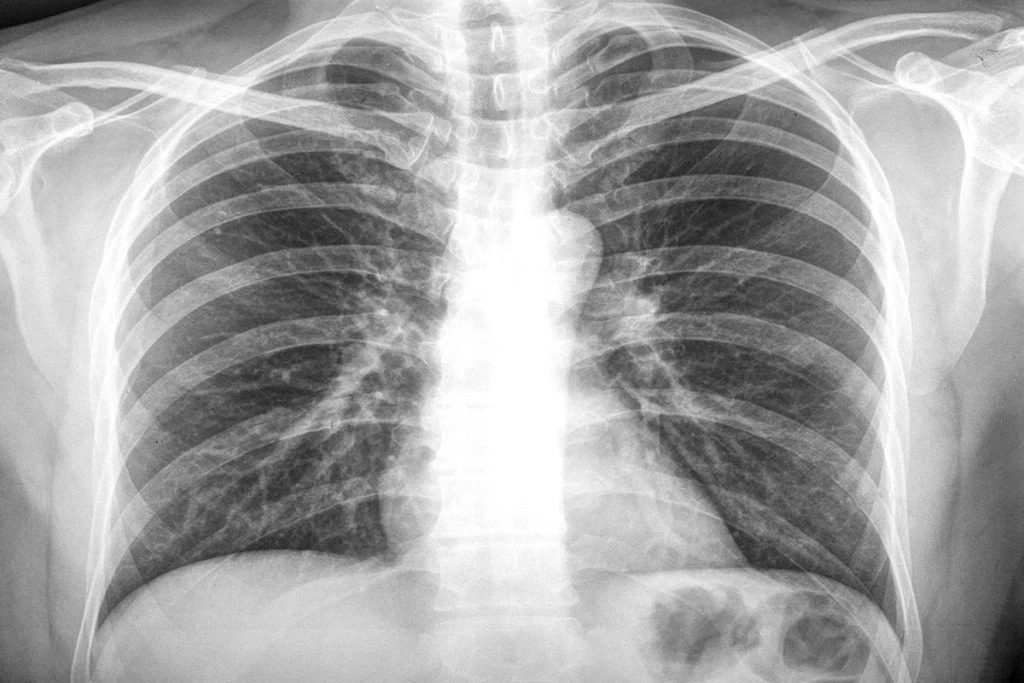

โรค "มะเร็งปอด" โรคนี้มีความน่ากลัวสักแค่ไหน ชวนคอข่าวเนชั่นออนไลน์ มาทบทวน ทำความรู้จักกับภัยร้ายภัยเงียบเจ้าโรคนี้ กันอีกครั้ง

"เนชั่นออนไลน์" ขอนำข้อมูลสาระดีๆ ข้อควรรู้เกี่ยวกับโรคร้าย ภัยรายชนิดนี้ว่า มีอาการบ่งชี้ สัญญาณเตือนแบบไหนบ้าง การรักษามีกี่วิธี ปัจจัยเสี่ยงที่จะทำให้เกิดโรคนี้ ทั้งนี้เพื่อหลีกเลี่ยง ป้องกัน ลดความเสี่ยงในการเกิดโรคร้ายนี้

มะเร็งปอด ถือเป็นมะเร็งที่พบมากที่สุดทั่วโลก สำหรับประเทศไทย ยังคงเป็นสาเหตุของการเสียชีวิตเป็นอันดับ 2 ของคนไทย (ในผู้ชายรองจากมะเร็งตับและเป็นอันดับ 1 ในผู้หญิง) แต่ละปีจะมีผู้ป่วยรายใหม่ประมาณ 17,222 ราย เป็นเพศชาย 10,766 ราย และเพศหญิง 6,456 ราย ในจำนวนนี้มีผู้เสียชีวิตประมาณ 14,586 ราย หรือคิดเป็น 40 รายต่อวัน

หากมีอาการที่เข้าข่ายของโรคมะเร็งปอด แพทย์จะทำการตรวจร่างกาย ตรวจเสมหะ เอกซเรย์ปอด หากพบความผิดปกติ อาจต้องทำการตรวจเพิ่มเติมเพื่อยืนยันการวินิจฉัย